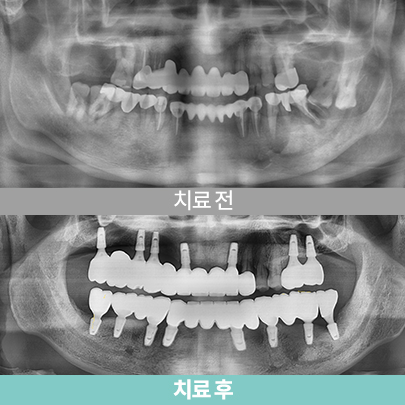

- 40대 남성, 치료 후 3개월

- 상·하악 풀마우스 임플란트

-

- 40대 남성, 치료 후 3개월

- 상·하악 풀마우스 임플란트

-